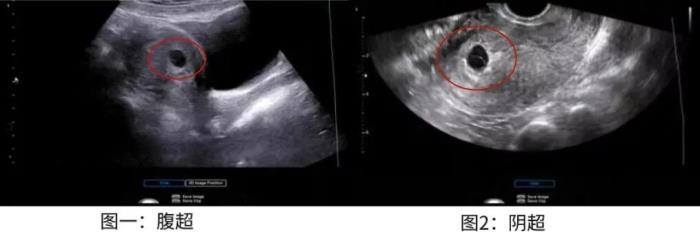

前两天就有一位孕妈来检查宝宝是否有胎心,因为不愿意做阴超,医生只好给她做腹超,结果腹超看不到胎心,只好再做阴超看一看,因为阴超能比腹超早1周发现胎心搏动。

终于这位孕妈在接受阴超检查时,看清了腹中已经萌芽的小小胎心。

这位妈妈做腹超和阴超检查的不同结果如下图,图1是腹超,图2是阴超,图中椭圆形黑色区域是孕囊,相比之下,明显可见阴超显示的孕囊要比腹部清晰很多。

图源:邦彦医院学习资料